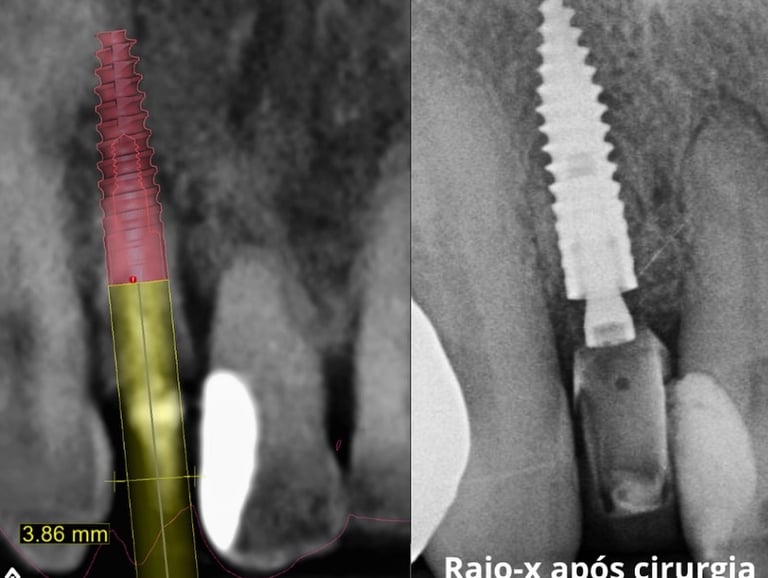

Curso especializado em técnicas de reabilitação com implantes dentários utilizando técnicas atualizadas e avançadas com planejamento digital em softwares específicos.